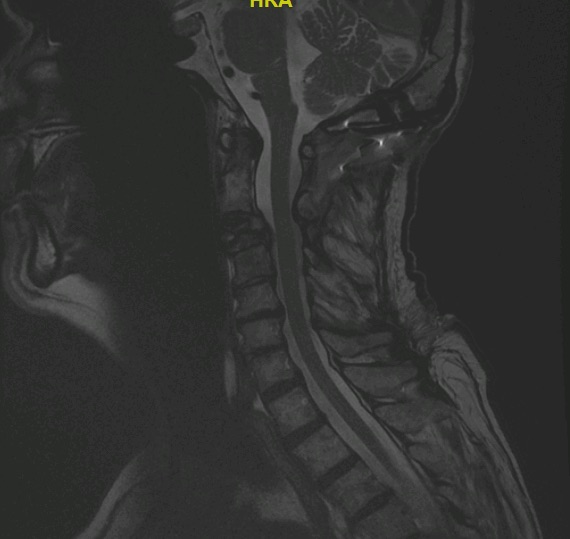

Paciente de 71 años que presenta enfermedad oncológica en estadio paliativo por tumor renal de años de evolución. Presentó fractura patológica C3 con clínica de tetraparesia súbita e incapacidad para mantener bipedestación (ASIA C). En comité de Neuroncología se acordó tratamiento quirúrgico paliativo.

Obsérvese afectación pedículo/pars C2 por el tumor